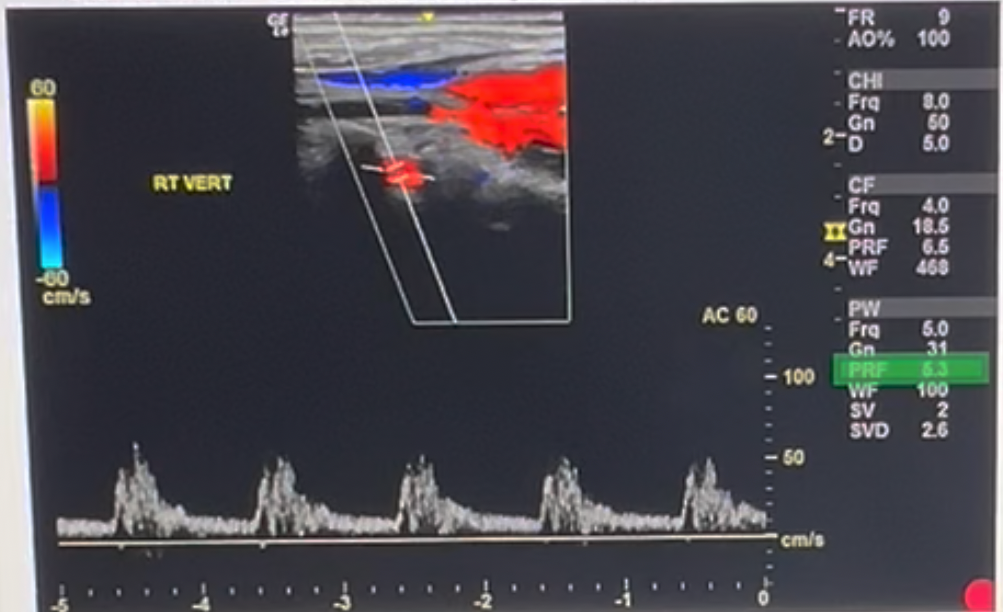

Review the image and the system settings listed along the right side. Use your mouse to position your cursor over the setting that should be adjusted to improve the diagnostic quality of the Doppler tracing. Click to set the cursor and conform your answer.

PRF